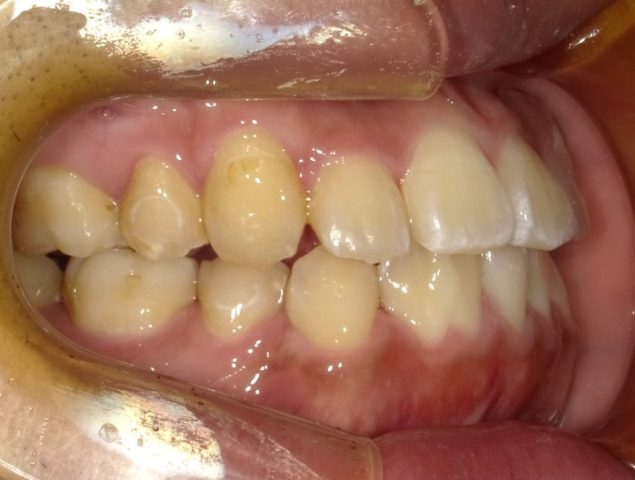

【右側面観】

2023年1月

永久歯生え揃い、身長の伸びも落ち着いてきたので

2段階目スタートします。

2023年1月(16歳8ヶ月)

顎の大きさに比べ、歯が大きいので抜歯してスタートします。